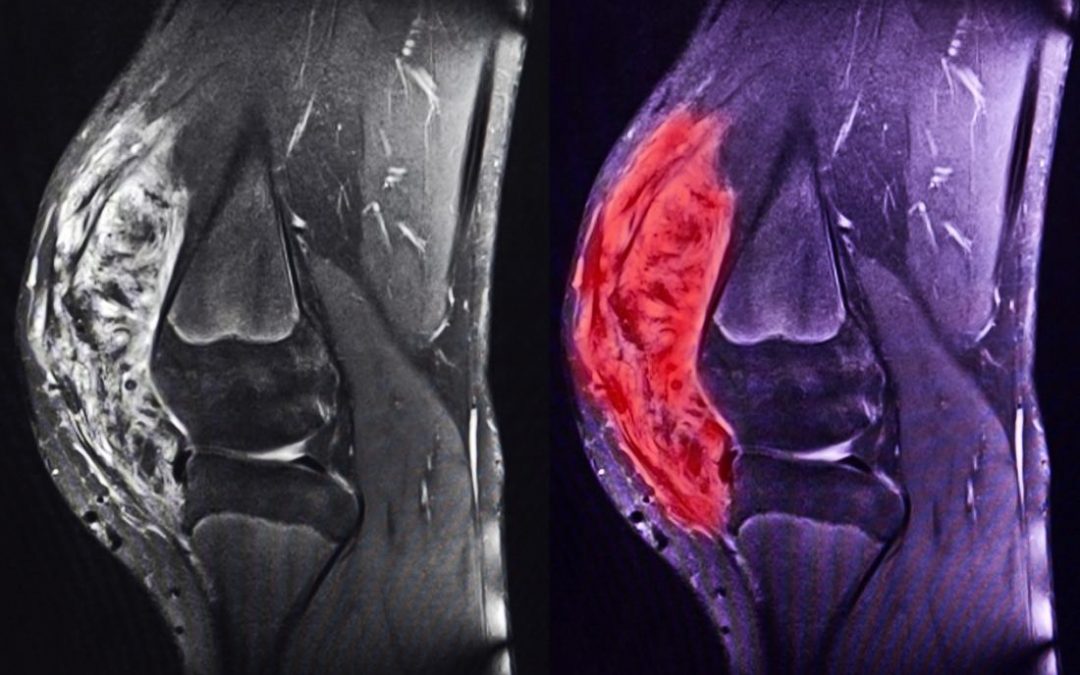

Si sono appena conclusi i due incontri dei centri Provider sui sarcomi ossei pediatrici (osteosarcoma e sarcoma di Ewing) tenutisi a Milano e Bologna, cui l’Aoup ha partecipato come centro di riferimento italiano ed europeo con i contributi di Luca Coccoli (Oncoematologia pediatrica), Alessandro Franchi (Anatomia patologica, responsabile del “Programma Creazione di un percorso diagnostico anatomo-patologico per le neoplasie dell'apparato muscolo-scheletrico”) e Lorenzo Andreani (Ortopedia e traumatologia 2, fra i referenti aziendali della rete Euracan - tumori rari solidi dell’adulto - per i sarcomi ossei e delle parti molli).

Scopo principale dell’incontro è stato infatti la stesura dei nuovi protocolli di trattamento, ossia le nuove linee guida in questo campo grazie all’elevato expertise maturato negli anni dall’Aoup in virtù dell’approccio multidisciplinare e personalizzato alle cure.